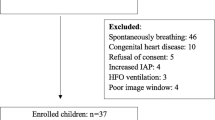

In this prospective observational study, fifty-eight spontaneously breathing sepsis patients admitted in the ICU (between May 2017 and April 2019) were enrolled in the non-probability consecutive sampling after the approval of the departmental Research Ethical Committee, and the informed written consent had been taken from the patients.

Patients with the following criteria were excluded from the study: clinical signs of hemorrhage, arrhythmia and cardiogenic or obstructive shock. Also, we excluded subjects in whom there was inability to postpone administration of fluid for several minutes or if the clinical staff feared that the patient had active pulmonary edema or there could be a clinical risk from further intravenous fluids.